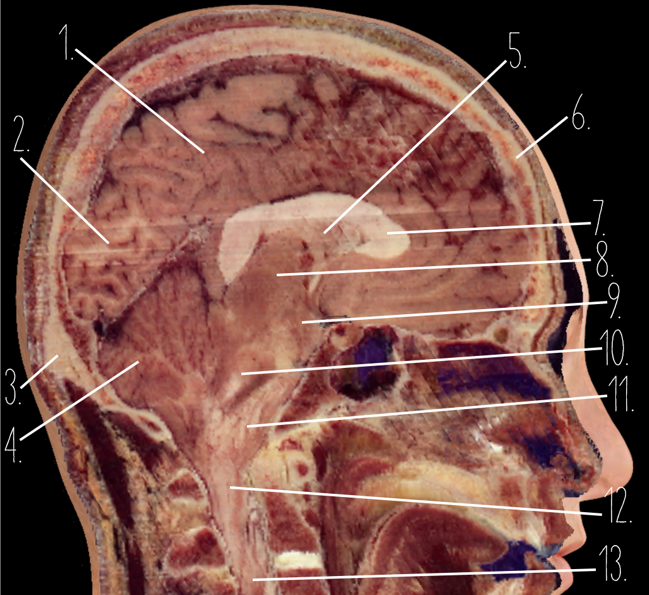

Brain Cross Sectional

1

Frontal Bone

2

Frontal Lobe

3?

Falx Cerebri

4?

Gray Matter

5?

White Matter

6?

Sulcus

7?

Gyrus

8?

Fissure

1?

Parietal Lobe

2?

Cerebellum

3?

Occipital Bone

4?

Cerebellum

5?

Lateral Ventricle

6?

Frontal Bone

7?

Corpus Callosum

8?

Thalamus

9?

Hypothalamus

10?

Midbrain

11?

Pons

12?

Medulla Oblongata

13?

Spinal Cord